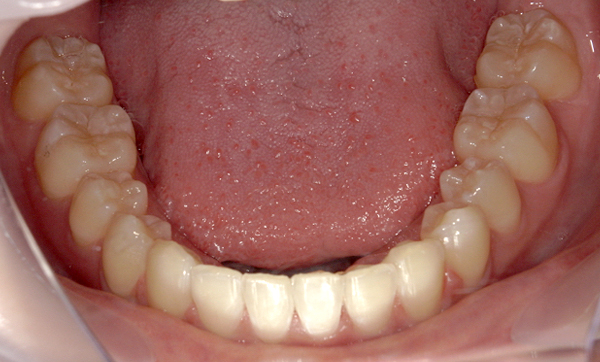

症例_008 「上下の前歯」症例

治療期間:13ヶ月金額:57万円+税40代女性捻転歯前歯のガタガタ

Before | After |